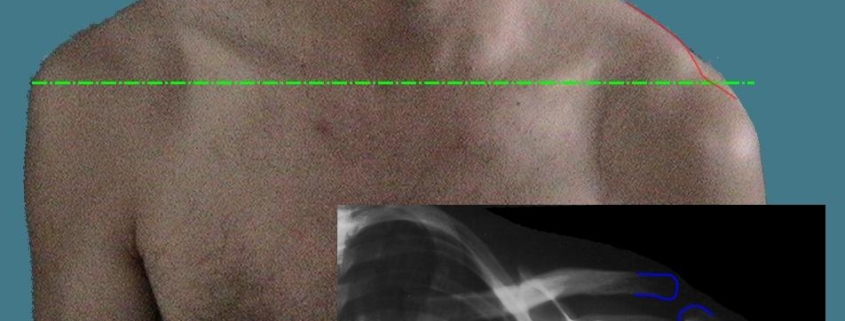

- A visible lump or bump at the top of the shoulder.

Diagnosing AC Joint Separation typically involves a physical examination and imaging tests. Doctors may ask about the patient’s medical history, details of the injury, and the symptoms experienced. Physical examination includes assessing the range of motion, strength, and tenderness of the shoulder. Imaging tests like X-rays, MRI, or ultrasound may be conducted to visualize the injury and determine its severity.